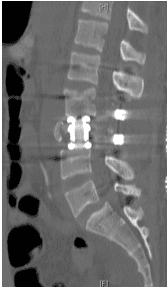

Un chico de 18 años se cayó desde tres pisos. Pérdida casi total de todas las funciones neurológicas por debajo del nivel de lesión con afectación casi total del intestino y la vejiga

Cirugía

El paciente fue operado y el conducto espinal limpiado de todos los fragmentos óseos. La columna vertebral se fijó de lado y la parte trasera para eliminar la inestabilidad.